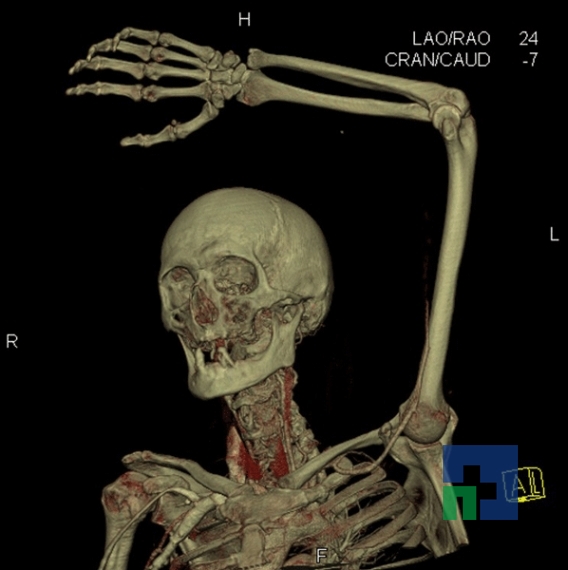

- Diagnosticul fracturilor:

- Unice

- Multiple

- Cu înfundare

- Complexe cranio-sinusale

- Complexe cranio-etmoidale

- Complexe cranio-orbitare

- Complexe cranio-faciale